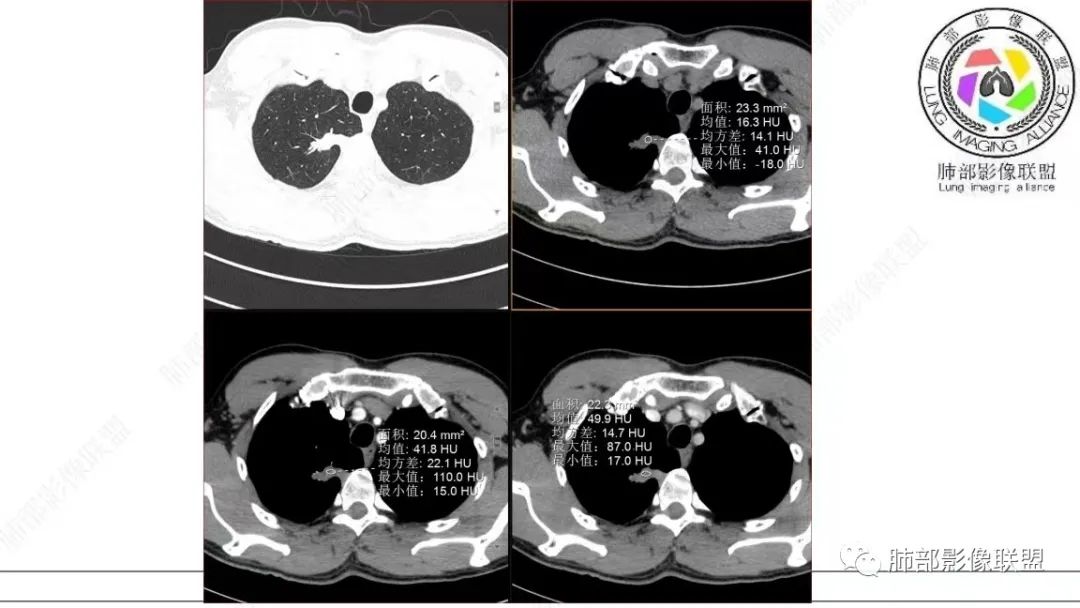

仔细看,里面是有低密度的。平扫CT值也很低,才16HU。

增强也很有特点。这些低密度,是有延迟强化特点的。

平扫低密度,就这个病变而言,我们最容易想到的:干酪性坏死、黏液。而延迟强化。所以这个病变是不符合干酪性坏死的表现的。很多平直凹陷的地方,与胸膜宽基底接触,是否存在胸膜牵拉不详,需重建看看。说明这个病变是有收缩力的。里面含有一部分纤维。当然,含有纤维的,肿瘤的肌成纤维可以,上皮间质转换可以,慢性炎也可以,好多病变里面可以有纤维。干酪样坏死,是不会强化的。延迟强化,肉芽肿可以,纤维比较多的或者黏液多的也可以。

还是和病变成分有关。在肿瘤当中,或者上皮间质转换比较明显等,可以有不同的强化方式。当然也可以表现为延迟强化,可以动脉期明显强化。和肿瘤的具体类型,以及具体病变的病理成分有关。多层面观察,病变是明确有细支气管进入的,而且明确的有铸型的低密度粘液栓。

在细支气管腺瘤的文献中,病例较少,没有看到过提到有粘液栓形成的病例描述。细支气管腺瘤的病理要点中,1,可以见到细支气管进入病灶。2.双层细胞。细支气管水平的病变,当然就可以有纤毛,有可以分泌黏液的细胞。在细支气管腺瘤中,形成的粘液,可以弥散在组织间隙,也可以聚集,形成粘液湖。更容易经过细支气管排出,形成空洞。类似于腺癌的空泡。这个病例虽然有延迟强化,收缩力比较强,也有支气管粘液栓,但是比较难解释这么低密度的,有延迟强化的,可疑粘液成分。

这个病例还可以深挖,图像有点少,我感觉部分层面可疑少许磨玻璃。最难鉴别的是结节型黏液腺癌,特别是细支气管腺瘤的收缩力比较弱的时候。这个病例收缩力太强,结节型黏液腺癌不太好解释。结合病理及影像表现,这个病例最终诊断:倾向于细支气管腺瘤、合并一些非特异性的感染、支气管内粘液栓形成。细支气管腺瘤,疑难。实性的细支气管腺瘤,更疑难。再合并感染,难上加难。不讲理的一个病例。